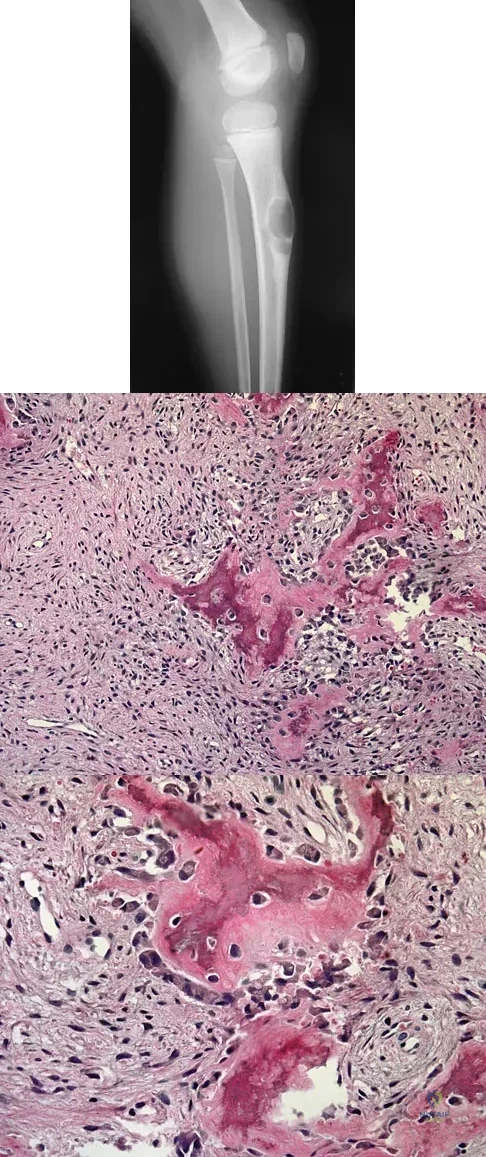

A 6-year-old boy presents with a mass and a lucent lesion involving the tibial shaft as seen in Figure 17a. The mass is mildly tender to palpation. The bone scan is focally hot in the tibia. Biopsy specimens are shown in Figures 17b and 17c. What is the most likely diagnosis?

Explanation